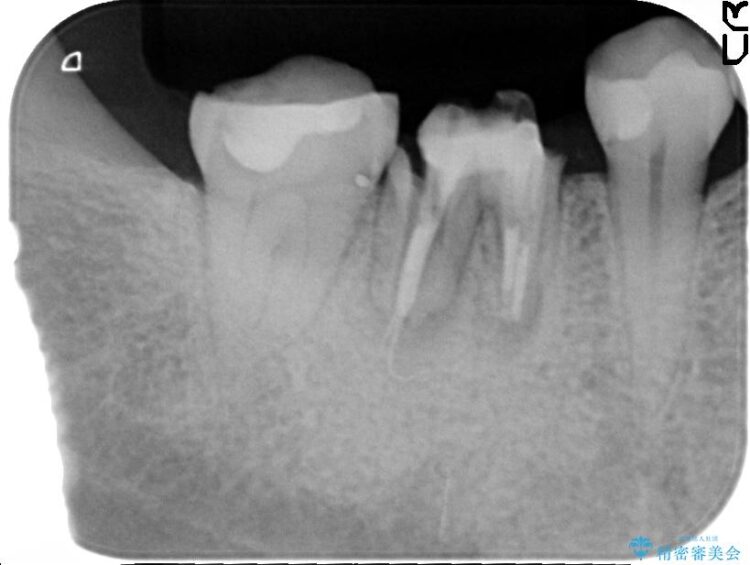

精密な検査を行ったところ、根が完全に折れている為、抜歯が必要となりました。抜歯後は骨と歯茎が痩せてしまう事がないように、人工の骨をつめ、インプラント治療を行う計画としました。

治療後について

抜歯を行った当日に骨の維持をする為、人工の骨を充填しました。インプラントを埋入する際には、ほとんどが自分の骨に置き換わっており、頬舌的なへこみを引き起こす事もなく、審美性・機能性ともに維持する事が出来ました。